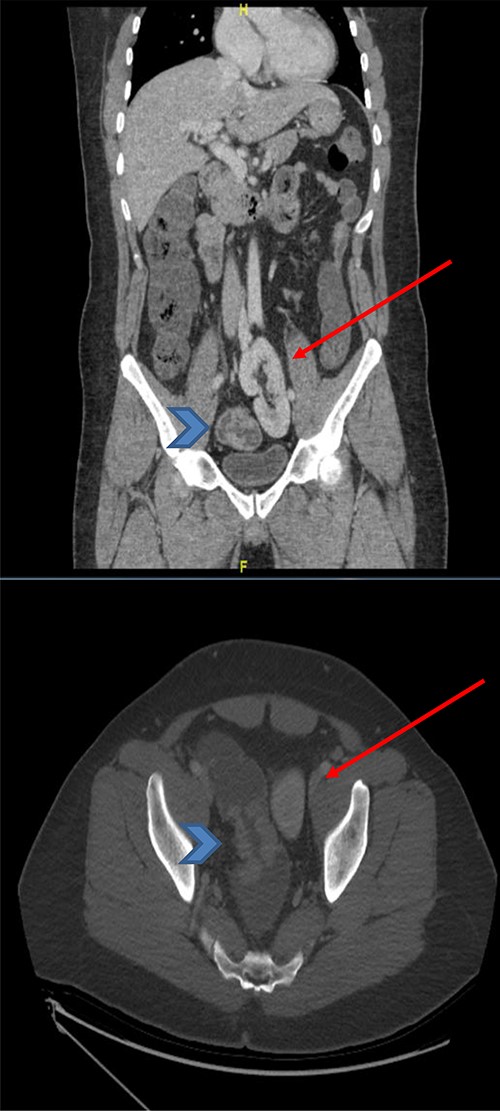

CT scan of the abdomen and pelvis (coronal and axial view) showing the upper rectal mass (arrowhead) with ectopic kidney (arrow), clear plane noted in-between without tumor invasion.